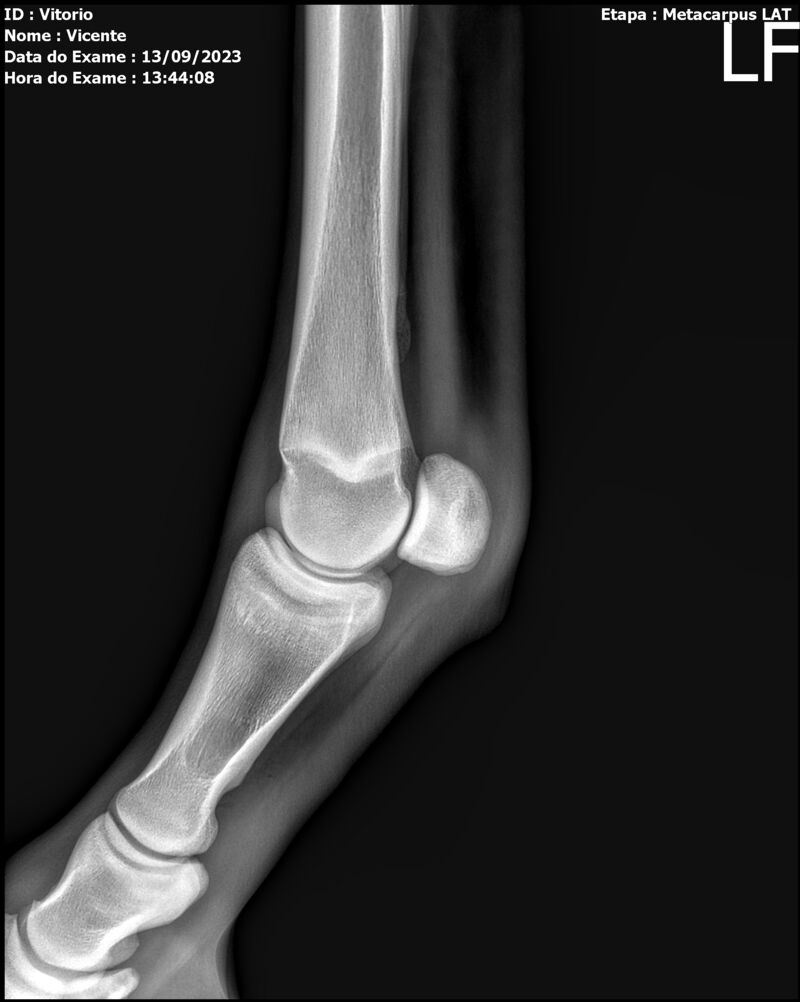

LOTE 13

THUNDER ZC

Raça: BRASILEIRO DE HIPISMO

Sexo: MACHO - POTRO

Nascimento: 17/09/2022

Altura Aproximada: 1,54

Pel.: CASTANHO

Registro: EM AND

Vend.: VICENTE CONTE

Local : PORTO FELIZ/SP